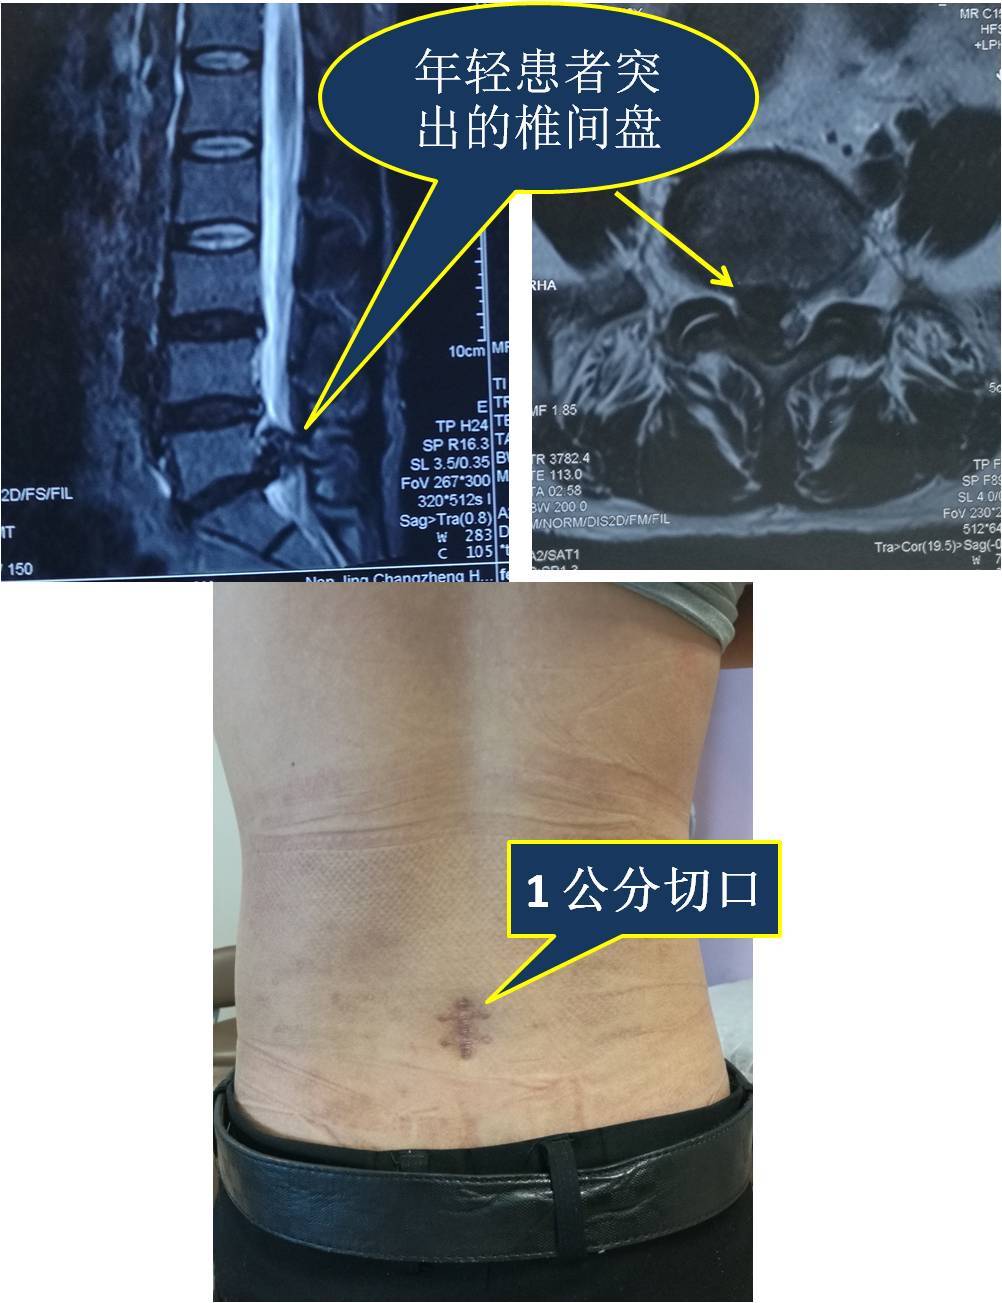

腰间盘突出症患者内镜治疗术后一年发来反馈

我的门诊病历:腰5骶1椎间盘突出症,保守治疗